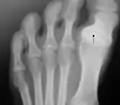

"Hallux varus is a clinical condition characterized by medial deviation of the great toe at the metatarsophalangeal joint. [abbreviation excised]".[1] This condition when acquired by adults is usually caused by sports injury, surgical overcorrection of hallux valgus, or underlying causes such as arthritides.[1]

In places where modern shoes whose toe boxes are excessively narrow have not been worn, the condition known as normal feet can be mistaken for hallux varus.

The "sandal gap" is a phenomenon in which, due to the lack of a restrictive toe box in sandals, the toes can actuate unrestricted, so one may end up with any number of aligned and misaligned toes depending on how often one uses either sandals or narrow toe box shoes at any given time throughout one's life.